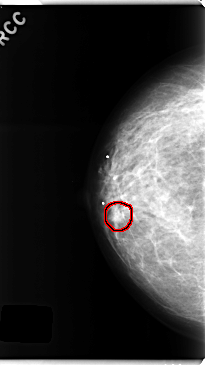

C_0252_1.RIGHT_CC

RIGHT_CC LINES 4744 PIXELS_PER_LINE 2656 BITS_PER_PIXEL 12 RESOLUTION 50 OVERLAY

FILE: C_0252_1.RIGHT_CC.OVERLAY

TOTAL_ABNORMALITIES 1

ABNORMALITY 1

LESION_TYPE MASS SHAPE OVAL MARGINS MICROLOBULATED

ASSESSMENT 4

SUBTLETY 4

PATHOLOGY BENIGN

TOTAL_OUTLINES 1

BOUNDARY